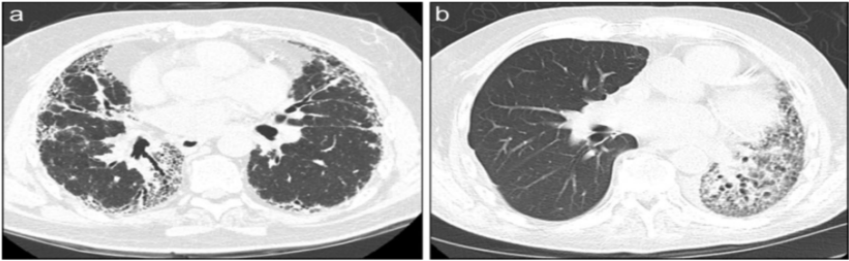

下图为ILD的基本影像学改变,如大片磨玻璃影、胸膜下实变影、蜂窝网格影等改变。

下图是ILD患者单侧肺移植术后3个月的随访胸部CT,可见右肺结构相对正常,但左侧肺的纤维化明显加重。

图片

图源:Respirology, 2016, 21(7):1173-1184.

下图是ILD双肺移植患者胸部CT,可见患者两肺结构相对正常,肺功能得到良好的保障。